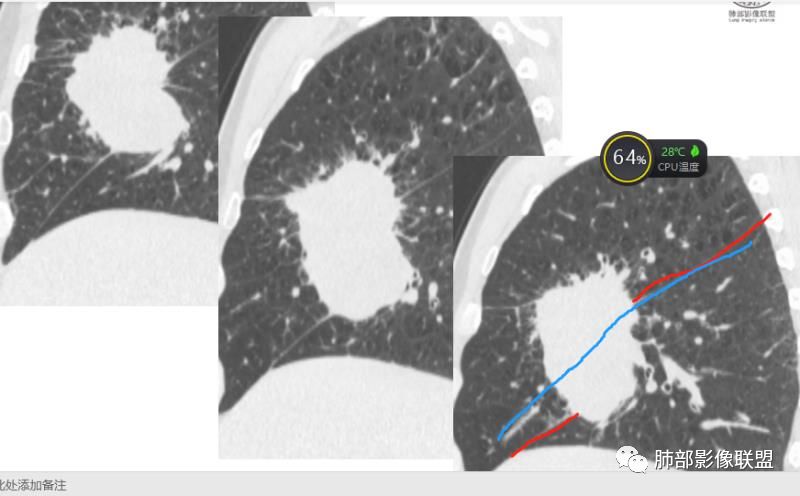

右肺巨大肿块,跨叶生长,其内见大片状坏死,坏死边界不清,血管进入,边缘受侵,病灶边缘可见毛刺及分叶,病灶强化方式速升速降,纵隔内见坏死强化淋巴结,周围肺叶小叶间隔结节样增厚,考虑恶性腺癌并淋巴结转移及癌性淋巴管炎,鉴别肉瘤。

患者中老年男性,体检发现肺部占位。

胸CT:右肺中叶实性占位性病变,呈膨胀性生长,对斜裂明显挤压,右肺中叶外侧段阻塞,并在边缘可见分叶、毛刺、棘突样改变,胸膜牵拉;增强可见病灶明显强化,可见边缘模糊血管影,病灶内可见大片状低密度区,隆突下可见肿大淋巴结。

诊断考虑:恶性病变。

右肺跨上叶与中叶一实性肿块影,中叶外侧段支气管堵塞,肿块有明显分叶、毛刺、棘突样改变,胸膜牵拉,周围有小花小草;增强可见病灶明显强化,病灶内可见大片状低密度区,以外侧为主,隆突下可见肿大淋巴结,恶性,考虑鳞癌可能。

患者中老年男性,体检发现右肺占位。血常规轻度贫血,AFP、CEA正常,肝肾功能、血糖、血脂、心肌酶、电解质正常。胸部CT:右肺中叶巨大肿块灶,垮叶生长,可见分叶、毛刺、血管集束、支气管截断征象,远端周围可见小叶间隔增厚,增强轻度强化,内可见低密度坏死区,综合淋巴结肿大,且可见淋巴结内似低密度灶。综合考虑恶性,鳞癌并癌性淋巴管炎可能大。鉴别结核、腺癌。

胸CT:右肺中叶团块样实性占位,边缘膨隆,中叶外侧段阻塞,病灶可见深分叶、棘突,胸膜牵拉;增强不均匀强化,可见边缘模糊血管影,病灶内大片状低密度区,纵隔多发肿大淋巴结。

诊断考虑:恶性病变,鳞?大细胞?鉴别:TB